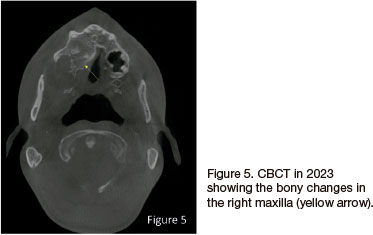

An 18-year-old male patient presented at our dental clinic in 2009 for a dental assessment. A panoramic radiograph was taken to evaluate dental crowning (Figure 1). An incidental finding was noted in the right maxilla, presenting as a well-demarcated, round, unilocular, radiolucent lesion with a corticated rim extending from the right maxillary tuberosity area to distal of the 16 causing impaction of the 18. A biopsy was taken and diagnosed as an odontogenic keratocyst (OKC) that was subsequently enucleated. In 2021 the patient returned and another panoramic radiograph (Figure 2) and a Waters view was taken where calcification of the falx cerebri was seen (Figure 3). On the panoramic radiograph an additional mandibular lesion was visible that presented as a well-demarcated, round, unilocular, radiolucent lesion with a corticated rim extending from distal of the 46 into the missing 47, 48 area. A CBCT was then taken to further analyse the lesions (Figure 4). A biopsy was taken in the right posterior mandible and diagnosed as an OKC. In 2023 the patient returned and a CBCT was taken. The right maxilla showed increased bone density adjacent to the enucleated lesion (Figure 5).